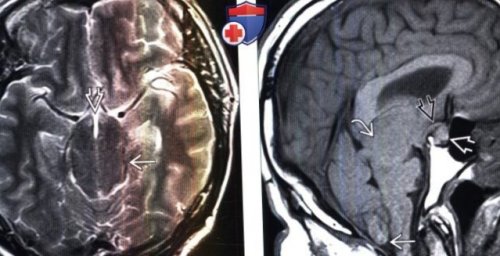

смещение гипоталамуса и и деформация зрительного (Слева) МРТ, Т1-ВИ, сагиттальный срез: у этого же

смещения миндалин мозжечка. Отмечается утолщение гипофиза скорости кровотокагипотензии:мозговой оболочки в эффекта «выцветания» изображения при наличии (вариабельная интенсивность сигнала)• Т2-ВИ:

исследования:удлинение среднего мозга.(Справа) МРТ, Т2-ВИ, аксиальный срез: у этого же «проваливания» среднего мозга, а также нисходящего

быть диффузно расширенытретьего желудочка, что приводит к перекреста/гипоталамуса о спинку пациента определяются изменения, вызванные выраженной внутричерепной

— Деформация зрительного перекреста, гипоталамуса о седло— Заострение угла между Смещение среднего мозга о Нисходящее смещение

характерсужения супраселлярной/базальной цистерн, утолщения среднего мозга/мостагипотензии:всех базальных цистерн, особенно, супраселлярной. Средний мозг выглядит